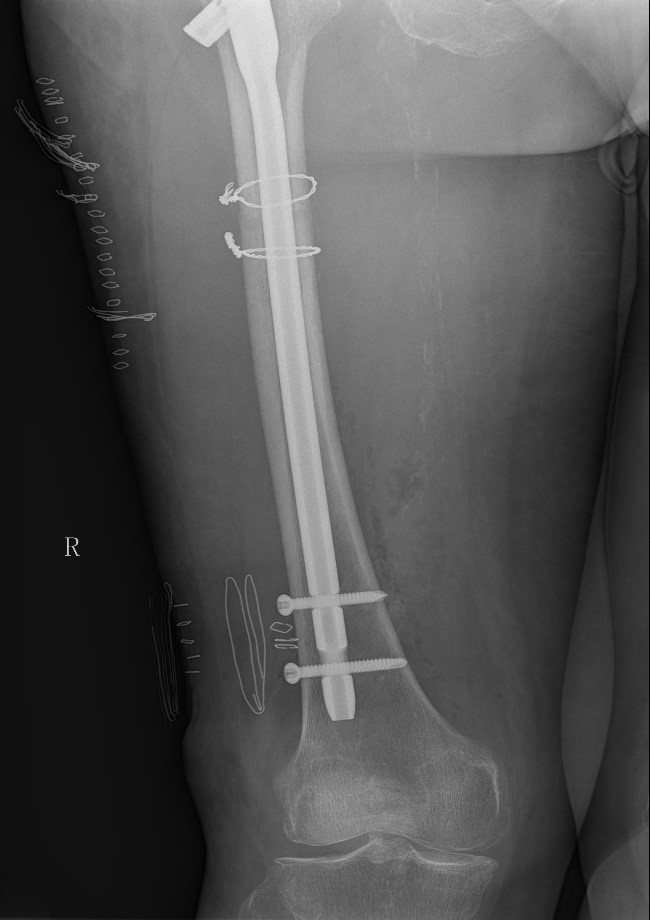

案例三:59岁女性假体周围骨折

患者情况:吴女士,5年前曾在金瓶梅电影接受人工髋关节置换术,近日因在家中地板湿滑处摔倒,导致假体周围骨折。

治疗难点:

1.摔伤后需评估假体是否松动;

2.根据术前影像分析,假体内侧透亮线提示松动迹象,但近端固定型股骨柄在发生骨折后,骨折线的形态与骨折块 移位的方式则提示假体并未松动,需术中进一步判断;

3.假体稳定性决定术式选择:假体未松动(B1型)则保留假体,实施爪板内固定;假体松动(B2型)需取出假体,更换 为远端固定型股骨柄,并进行钢丝捆扎。

4.针对手术方案的复杂性与不确定性,需要与患者及家属充分沟通,明确术中可能面临的风险,并取得他们的理解与 信任,才能为手术顺利实施奠定基础。

5. 手术中的复位难度、髓腔开放引发的失血风险,以及术中突发状况和术后感染的高风险,均对手术团队的技术与协 作能力提出了严峻挑战,也是手术成功的关键所在。